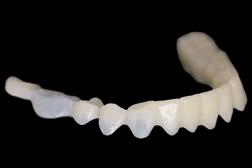

5: A treatment mock-up may be fabricated in a flexible machinable polycarbonate based on the contours of a final proposed restoration, in such a manner as to be capable of fitting to the contours of the pre-operative situation.

At the laboratory, the dental technician may merge these digitised records using Zirkonzahn.Modifier software (Zirkonzahn Srl; Gais, Italy) to form a precise 3D rendering of the patient’s pre-operative dentofacial situation, with all biomechanical and aesthetic landmarks conveniently available for reference. This offers the technician unparalleled, high-fidelity access to key diagnostic clinical information when compared to conventional analogue-based workflows.4 At this stage, an end goal of prosthodontic treatment may be developed wherein the contours of the proposed restorations are informed on the basis of the patient’s physiognomy, or rather, their unique and characteristic facial features (Figure 4).9 The final proposed design may be fabricated into a snap-on smile try-in, or treatment mock-up, using a flexible machinable polycarbonate (Temp Premium Flexible; Zirkonzahn Srl, Gais, Italy) (Figure 5).

At this early stage of diagnostic work-up, prior to any operative intervention, the clinician and the technician can now communicate to each other and, most importantly, to the patient, in an understandable visual rhetoric, a precise end goal of treatment from which a meeting of the minds may be achieved (Figures 6 and 7).5